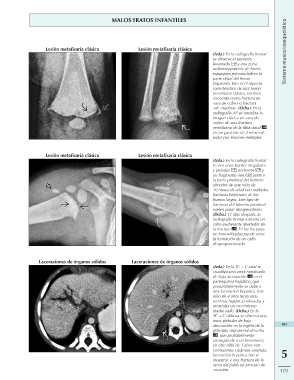

Lesión metafisaria clásica Lesión metafisaria clásica (Izda.) En la radiografía frontal

Lesión metafisaria clásica se observa el periostio

Laceraciones de órganos sólidos levantado y una zona

radiotransparente de hueso

esponjoso primario en la

parte distal del fémur

izquierdo. Este es el aspecto

característico de una lesión

metafisaria clásica, también

conocida como fractura en

«asa de cubo» o fractura

«de esquina». (Dcha.) En la

radiografía AP se visualiza la

imagen clásica en «asa de

cubo» de una fractura

metafisaria de la tibia distal

en un paciente de 2 meses de

edad con lesiones múltiples.

Lesión metafisaria clásica (Izda.) En la radiografía frontal

se ven unos bordes irregulares

y peludos , esclerosis y

un fragmento óseo junto a

la parte proximal del húmero

derecho de este niño de

10 meses de edad con múltiples

fracturas bilaterales de los

huesos largos. Este tipo de

fracturas del húmero proximal

suelen pasar desapercibidas.

(Dcha.) 11 días después, la

radiografía frontal muestra un

callo exuberante alrededor de

la fractura . En las fracturas

no inmovilizadas puede verse

la formación de un callo

desproporcionado.

Laceraciones de órganos sólidos (Izda.) En la TC + C axial se

visualiza una zona ramificada

de baja atenuación en el 491

parénquima hepático, que

presumiblemente se debe a 5

una laceración hepática. Este

niño de 4 años tenía unas 119

enzimas hepáticas elevadas y

mostraba un crecimiento

inadecuado. (Dcha.) En la

TC + C oblicua se observa una

zona globular de baja

atenuación en la región de la

glándula suprarrenal derecha

, que probablemente

corresponde a un hematoma,

en este niño de 3 años con

contusiones cutáneas extensas,

laceración hepática (no se

muestra) y una fractura de la

rama del pubis en proceso de

curación.